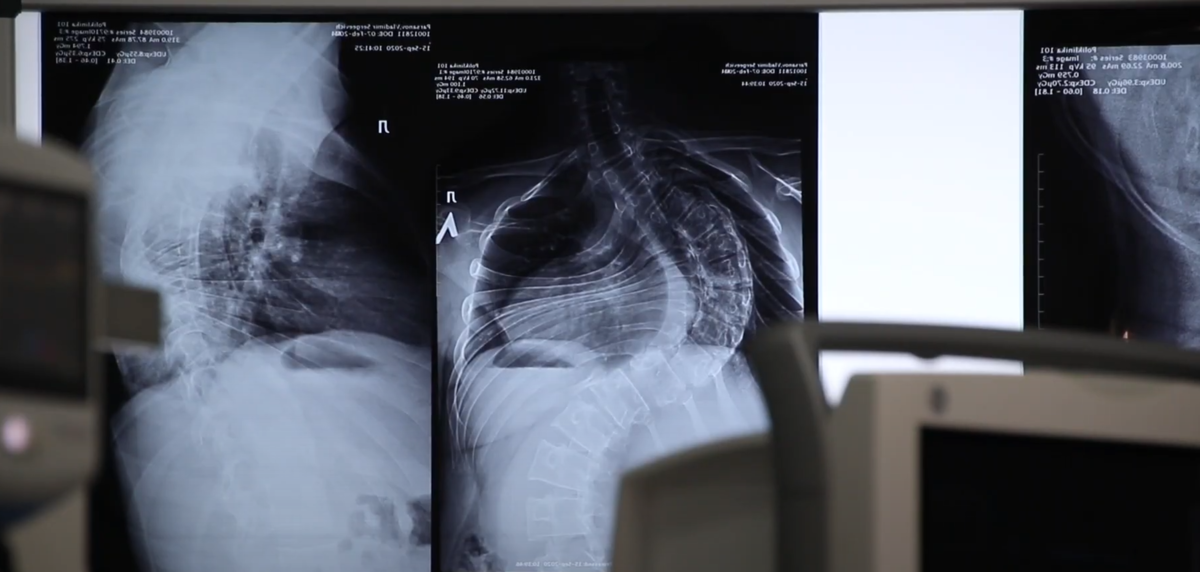

Сколиоз — искривление позвоночника в трех плоскостях. При патологии происходит ротация позвонков, меняется форма позвоночного столба. На теле становится заметной впадина с одной стороны и выпуклость (горб) с другой. Пациентам до 19 лет с искривлением менее 40 градусов сколиоз лечат консервативными методами. После 19 лет, когда прекращается рост костно-мышечных структур, если искривление позвоночника превышает 40-50 градусов, рекомендуется хирургическое лечение сколиоза. При такой деформации консервативные методы неэффективны. Операция при сколиозе проводится в несколько этапов: Степень травматичности операции, объем кровопотери, и длительность реабилитации зависит от нескольких факторов. Большую роль играет техника хирурга, используемые для операции инструменты, качество имплантов. Операция по устранению сколиотической деформации в центре ортопедии профессора Сампиева длится 2-3 часа, кровопотеря составляет 200-300 миллилитров. На следующий день после операции пациент встаёт, на 7-е

Сколиоз — искривление позвоночника в трех плоскостях. При патологии происходит ротация позвонков, меняется форма позвоночного столба. На теле становится заметной впадина с одной стороны и выпуклость (горб) с другой.

Пациентам до 19 лет с искривлением менее 40 градусов сколиоз лечат консервативными методами. После 19 лет, когда прекращается рост костно-мышечных структур, если искривление позвоночника превышает 40-50 градусов, рекомендуется хирургическое лечение сколиоза. При такой деформации консервативные методы неэффективны.